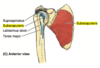

Subscapularis

origin: subscapular fossa of scapula (anterior)

insertion: lesser tubercle of humerus

innervation: upper & lower subscapular nn (C5-C7)

actions:

control ER of humerus (functional action)

IR & adduction of humerus

*part of rotator cuff (provide dynamic stability via eccentric contraction for shoulder stabilization/re-enforcement of GH joint capsule)